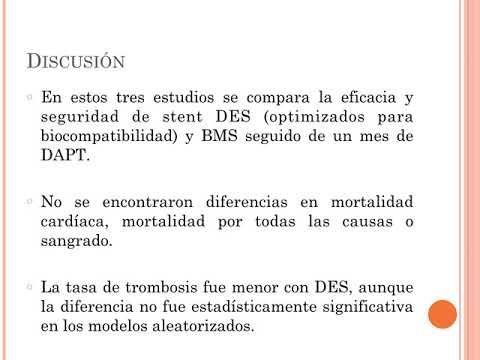

Eficacia y seguridad de los stent liberadores de droga optimizados por biocompatibilidad vs. stent metálicos con solo un mes de doble antiagregación. Dra. Florencia Cichello. Residencia de Cardiología. Hospital C. Argerich. Buenos Aires